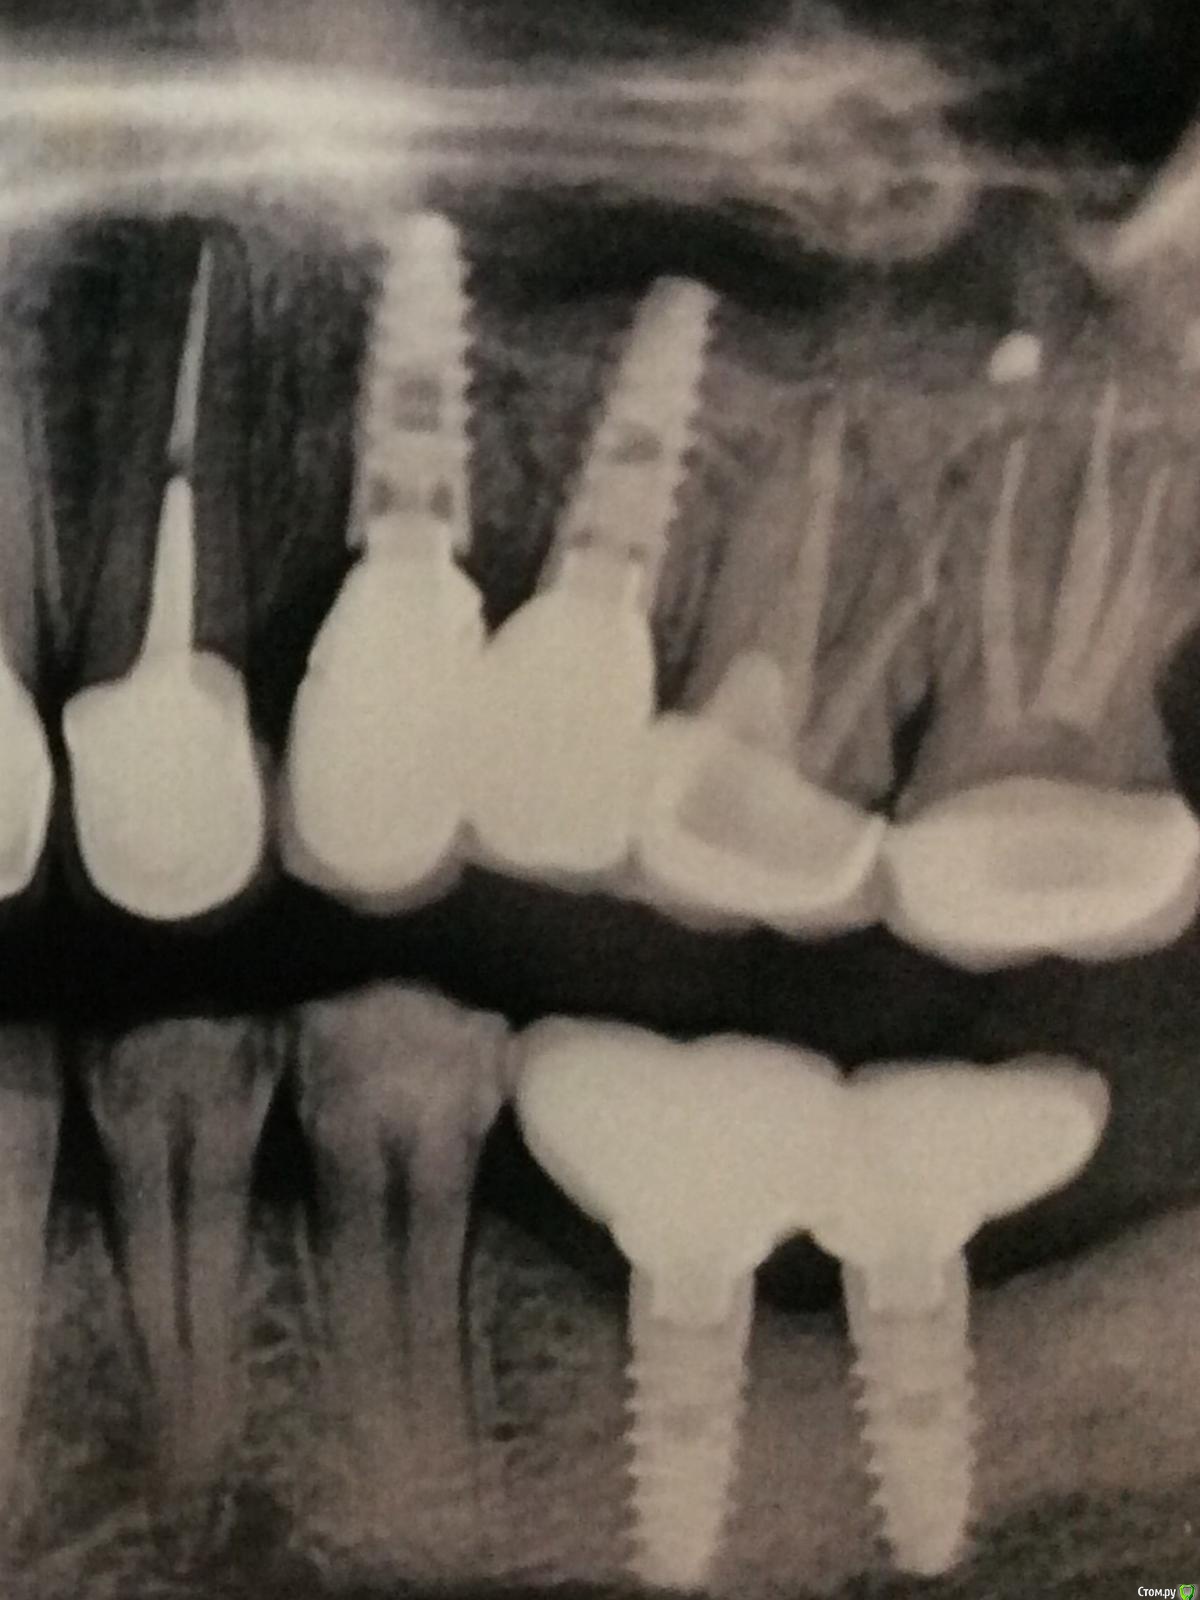

Dent8 Опубликовано 13 декабря, 2014 Поделиться Опубликовано 13 декабря, 2014 Уважаемые коллеги,обратился пациент с подвижностью мк конструкции.при осмотре снимка и полости рта видно мк 2.4. 2.5 (связаны между собой) с опорой на имплантаты,цементная фиксация.раскрутился винт.какая система пациент не в курсе,протезировался 5 лет назад в другом городе.посоветуйте правильное решение обойтись малой кровью,аккуратно попробовать сделать шахту в коронке и добраться до винта,или если не получится,полностью коронки придется распиливать? Ссылка на комментарий

Dent8 Опубликовано 13 декабря, 2014 Автор Поделиться Опубликовано 13 декабря, 2014 Снимок Ссылка на комментарий